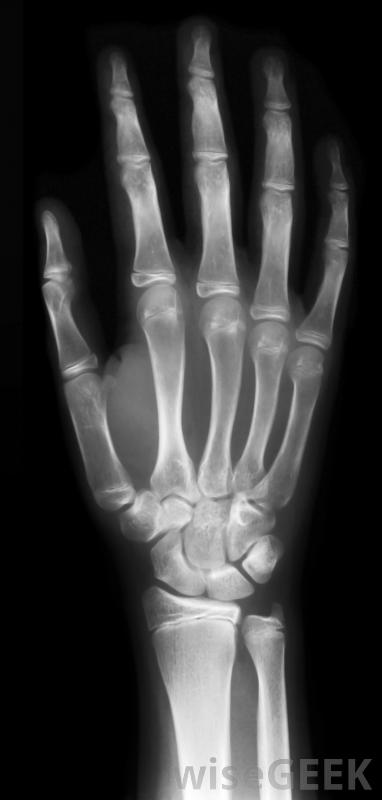

紧急护理是指为患有需要医疗护理的病人提供的医疗保健,最好在24小时内。与紧急护理不同,紧急护理必须立即提供,以防止永久性残疾或死亡,紧急护理涉及可能导致并发症的疾病,但不会危及生命。此类医疗护理的一个例子是为喉咙痛的患者提供帮助。X光可以在紧急护理机构进行通常情况下,这种类型的护理是在独立于医院的诊所中提供的,其理念是,当门诊患者无法预约常规医生,且病情不严重,不值得进行紧急护理时,他们可以前往紧急护理机构去急诊室。紧急护理医生充当普通医生的替身,而该机构通过处理非急诊病例来减轻急诊室的负担紧急护理设施可以通过接收无生命危险疾病的患者来减轻急诊室的负担,这些类型的护理设施在20世纪70年代开始激增许多健康保险公司强烈鼓励他们的客户尽可能使用紧急护理,因为这样可以降低成本,并确保在达到紧急医疗级别之前就得到治疗。例如,在24小时内治疗喉咙痛是非常容易控制的,但如果忽视它,它可能会成为一个紧急医疗事件。通过提供这种级别的医疗服务,医生可以迅速干预。一些医疗机构接受不定期访问,虽然在医疗机构人满为患的时候可能会有短暂的等待。其他人要求人们预约,但他们保证在24小时内预约。任何试图在24小时内预约医生的人都知道,能在一天内就诊会带来很大的不同。根据医疗机构的水平,这些诊所可能会提供各种各样的服务。在需要的时候,如果情况比原先想象的更严重,该设施可以将患者转诊到医院进行紧急护理。该设施还可以在实验室进行基本的医学测试,还可以包括一些医疗成像设备,如x射线和超声波,以用于诊断病人在急症治疗后,可建议他或她到正规医生或全科医生进行随访。如果病人的病例需要特殊技能,该机构可能会提供转介给一名专家,该专家将负责后续护理。